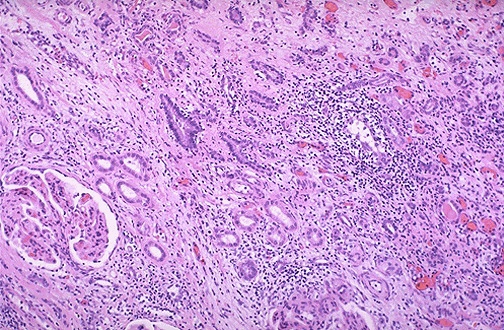

| Seen here is acute tubulointerstitial cellular rejection of a renal transplant. This can occur days to months to years following transplantation. Both CD4 and CD8 lymphocytes participate in this rejection reaction. The immunosuppressive drugs such as cyclosporine given to counteract the rejection may lead to nephrotoxicity with similar changes as well. |